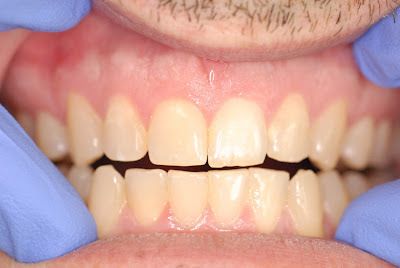

This 41 year old male patient came to our office for a second opinion regarding an implant. In 5th grade he had trauma to his front tooth #9. He had root canal treatment at that time and has never had a problem until 3 months ago.

The discoloration of #9 is very obvious, however, it has never really bothered the patient.

After course of antibiotics and bleaching treatment, the tooth is asymptomatic, less mobile and fully functional again.

I can't imagine anyone arguing that an extraction an implant is a better approach for this patient, but unfortunately there are some with that opinion. I think this may be partly due to a misinformed view of endodontic retreatment. In this particular case, you can see that the original RCT, which lasted only 30 years, without any crestal bone loss was a porous obturation. With normal probing depths and no signs of fracture, retreatment is obviously the best choice. If there are any of you with differing opinions, please share them with us.